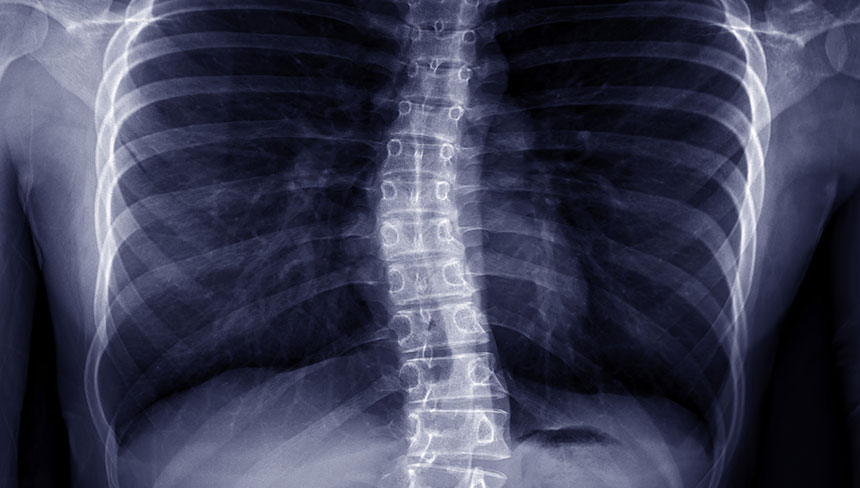

Does your child have scoliosis? We understand how much it can interfere with their daily tasks such as standing, sitting, walking, or even breathing. Finding relief from scoliosis can be a daunting journey with limited treatment options.

Living with scoliosis can have a tremendous impact on your child's life, from their emotional state to their ability to perform mundane tasks. Scoliosis is one condition that should be actively managed, or it may worsen if left untreated.